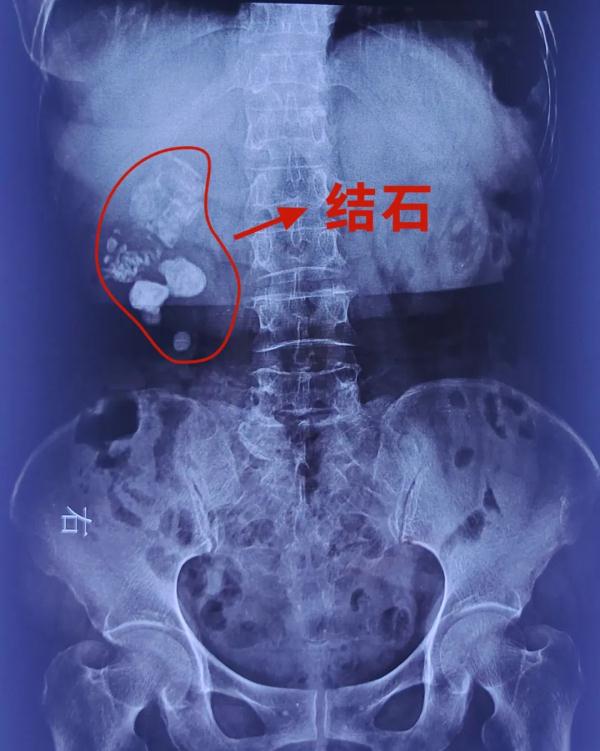

由于黄娭毑这一情况已持续有六七个月,在儿女陪同下来到了长沙南湖医院结石中心。经过检查发现黄娭毑的右肾内出现严重感染形成脓肾,肾脏更是布满结石,三四个核桃大的巨石非常显眼,周围脓苔如盘丝结网密密麻麻,情况非常严重。

“这个病人肾结石的病史有二十多年了,但是并没有进行有效的处理。寒颤、发热这些症状说明这个结石引起了严重感染,像病人这种情况,如果不治疗的话,感染还会反复发作,甚至引起脓毒败血症、感染性休克。另外,她感染性结石会越来越大,会造成肾脏严重积水,肾功能会马上丧失。”长沙南湖医院结石中心陈健教授表示。

经南湖医院结石中心专家研究后,医生为黄娭毑控制感染后已顺利完成一期经皮肾镜钬激光碎石取石术,取出大部份结石。